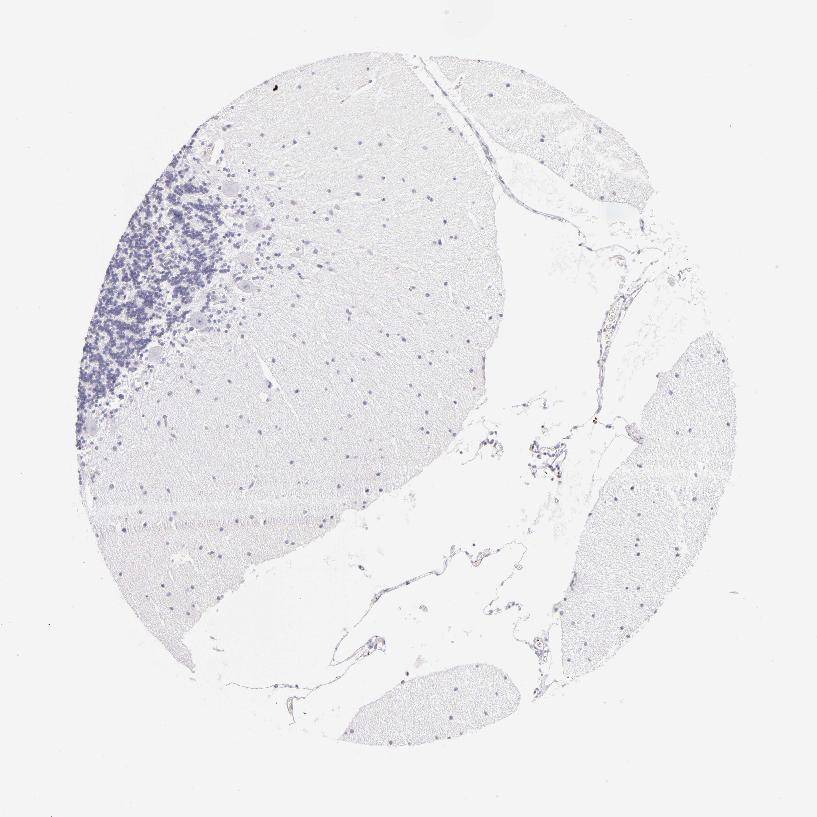

BRAIN CEREBELLUM Show tissue menu

CEREBELLUM - Antibody stainingi

Antibody staining in the annotated cell types in the current human tissue is reported as not detected, low, medium, or high, based on conventional immunohistochemistry profiling in selected tissues. This score is based on the combination of the staining intensity and fraction of stained cells.

Each image is clickable and will lead to virtual microscopy that enables deeper exploration of all samples and also displays staining intensity scores, fraction scores and subcellular localization as well as patient and tissue information for each sample.

Antibody HPA013316Antibody CAB002496

Purkinje cells Not detectedNot detected

Cells in granular layer Not detectedNot detected

Cells in molecular layer Not detectedNot detected